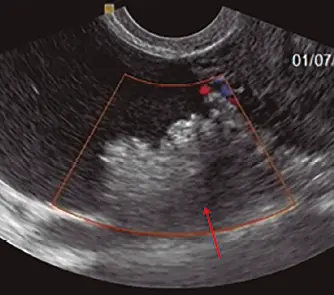

Fig: 9–a

Fig: 9–a, Se observa una formación mixta: sólida (flecha gruesa) y quística (indicadores, existen tabiques con grosor variables, algunos mayores de 3. 0 mm (flecha).